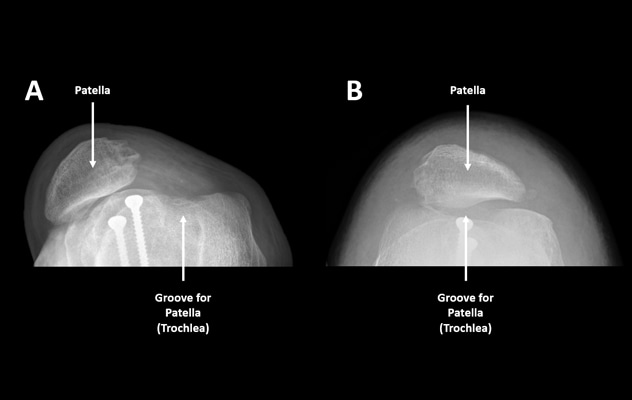

Patient before (A) and after (B) patellar stabilization surgery. Note how the patella lines up with the trochlear groove after MPFL reconstruction and soft tissue realignment.

Nonsurgical treatment options such as physical therapy may successfully treat some people with patellofemoral instability. However, Dr. Hevesi notes that in many instances, surgery involving restoration of the normal soft tissue restraints or "guides" of the patella, such as medial patellofemoral ligament (MPFL) reconstruction, are crucial to achieving and maintaining patellofemoral stability.

Surgical treatment for this condition usually involves reconstruction of the MPFL, which can be thought of as a soft tissue "seatbelt" that guides the patella into the trochlear groove of the femur. For patients with complex underlying anatomy, treatment also may include trochleoplasty, which is a reshaping of the trochlear groove, or an osteotomy, which is a realignment, of the femur or tibia.